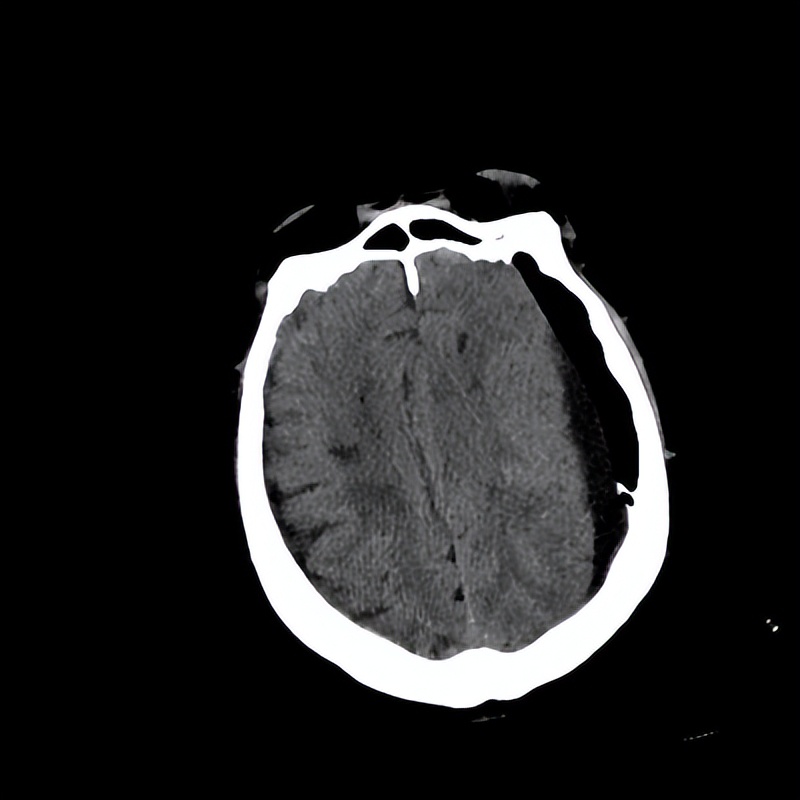

图四:术后复查CT示血肿彻底清除

术中,梁洪生教授治疗团队在手术室及麻醉医生的配合下,井然有序地开展。小“窗口”快速进入硬膜下血肿腔,此时神经内镜发挥了直视的优势,将全部血肿间隔打通、准确且快速吸除,明确出血点给予精准电凝止血;清除血肿后在内镜360°全方位无死角地观察无活动性出血后置入引流管,整个手术仅用20分钟顺利完成。术后赵大爷意识情况明显好转,语言流利,肢体肌力完全恢复,术后复查头部CT显示硬膜下血肿完全清除,脑组织受压情况明显改善,手术获得圆满成功。